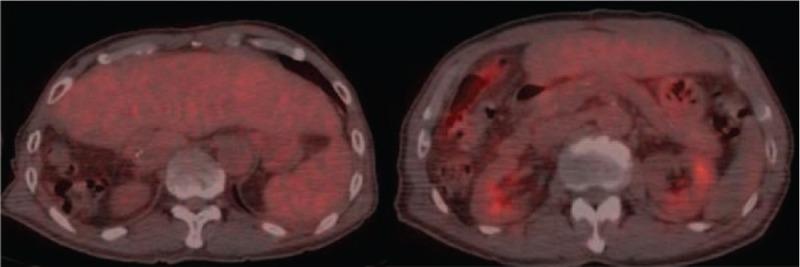

Metastatic hepatocellular carcinoma (HCC) of the right ventricle is very rare and difficult to diagnosis.A 79-year-old man who underwent right hemi-hepatectomy for HCC was admitted to our hospital for chest pain, severe dyspnea, and orthopnea. The echocardiogram showed a tumor located in the right ventricle. A biopsy was obtained, and histopathological findings confirmed metastatic HCC. Palliative resection of the tumor was performed.There is no standard treatment for metastatic HCC into the right ventricle. Thus, treatment should be individualized to the patient, and a multidisciplinary approach should be used.

右心室转移性肝细胞癌(HCC)非常罕见且诊断困难。一名因HCC接受右半肝切除术的79岁男性因胸痛、严重呼吸困难和端坐呼吸入住我院。超声心动图显示右心室内有一个肿瘤。进行了活检,组织病理学检查结果证实为转移性HCC。对肿瘤进行了姑息性切除。对于转移至右心室的HCC尚无标准治疗方法。因此,治疗应根据患者个体情况而定,并采用多学科方法。